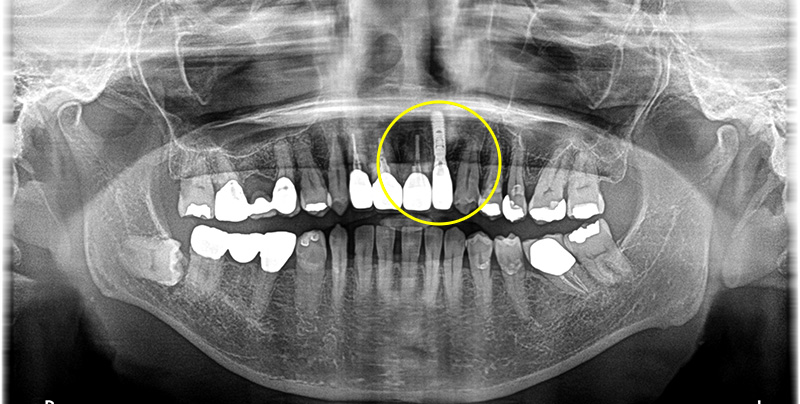

術後は定期的にチェックを行い、5ヶ月起き、インプラント体と骨が結合していることが確認できてから上部、他の前歯部の印象も行いました。

次に被せ物ができてからインプラント上部とクラウンのセットを同日に行いました。

術後は見た目も綺麗になりか大変満足していただいています。